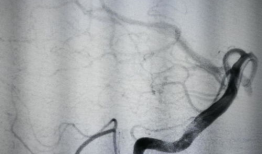

造影视频全过程,揭示血管奥秘与诊疗过程

你知道吗?最近我在网上看到一个超级有趣的造影视频全过程,简直就像是一部迷你电影,让我忍不住想要和你分享一下。这个视频详细记录了整...